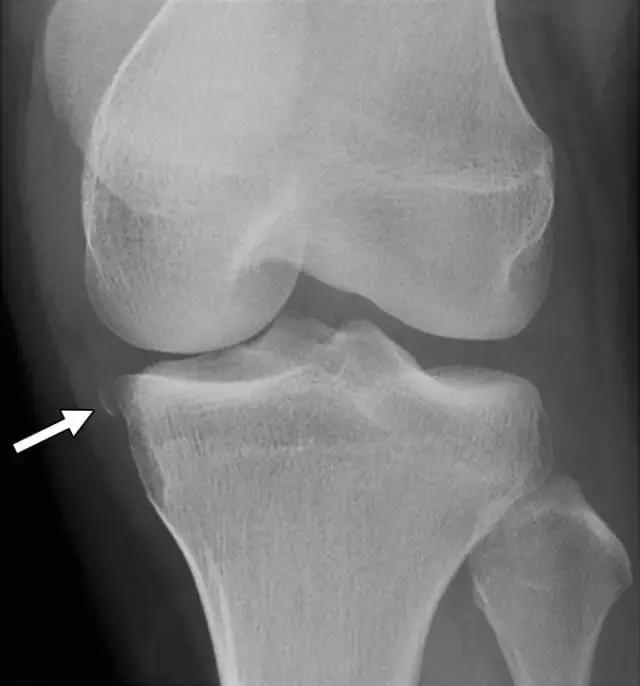

反向Segond骨折,是内侧胫骨平台的撕脱骨折,它是后交叉韧带严重受损的标志。这种骨折中的放射学检查结果与经典Segond骨折相似,只是反向骨折涉及胫骨近端的内侧(图6A)。据认为是由于内侧副韧带的深部荚膜组分的撕脱引起的(图6B),并且经常与内侧副韧带的严重损伤和相邻内侧半月板的周边损伤有关。

图6A -18岁的女性患有反Segond骨折。膝盖倾斜放射照片显示沿内侧胫骨平台的小撕裂性骨折(箭头)。

图6B,冠状脂肪抑制T2加权MR图像显示内侧胫骨平台内有明显的骨髓水肿,与内侧副韧带深部囊膜组分相关的反向Segond撕脱性骨折(箭头)。